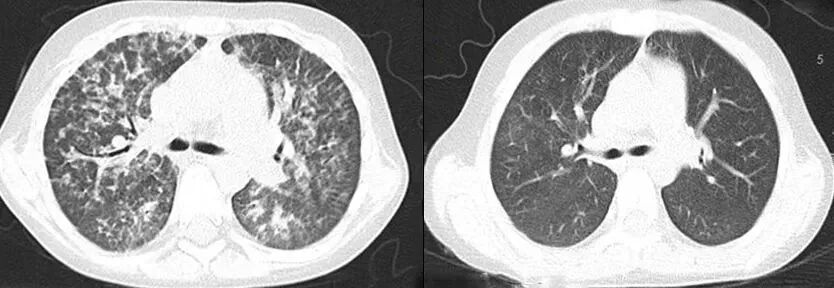

术前(左侧)和术后(右侧)的CT对比

移植后4年中,患儿一直随访治疗,在减停激素及免疫抑制药物后,病情没有复发,没有出现严重的移植相关排斥反应,术前(左侧)和术后(右侧)的CT对比,肺泡蛋白沉积症状显著改善术前(左侧)和术后(右侧)的CT对比,肺泡蛋白沉积症状显著改善,噬血细胞综合征表现迅速缓解,系统性红斑狼疮和肺泡蛋白沉积症的症状显著改善,肝脾明显缩小,代谢、免疫方面各项指标陆续从增高上百倍恢复到正常水平,身体状况平稳。